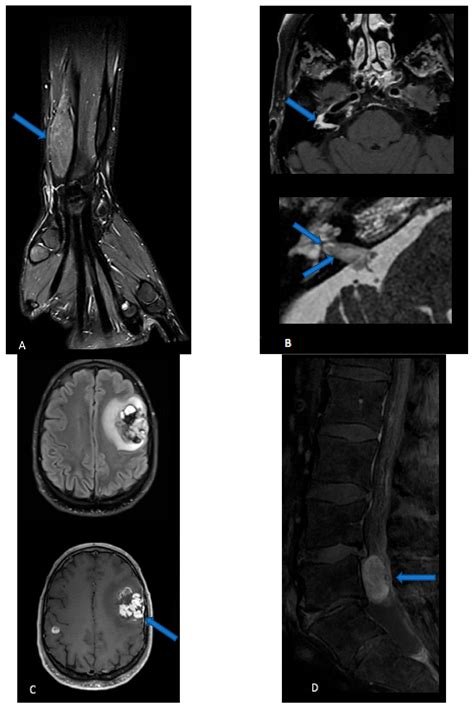

Magnetic Resonance Imaging (MRI) Provides high-resolution images of soft tissues, ideal for visualizing nerves.

Computed Tomography (CT) Used to see how the tumor interacts with surrounding bone structures.

• nerve sheath tumor radiology